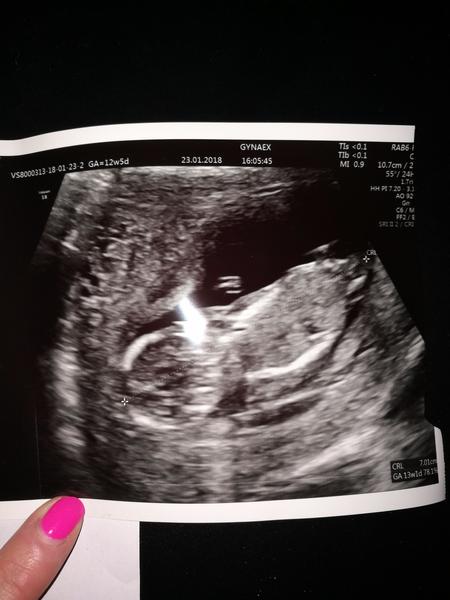

Tak tu je nás pokladik ❤️ Krásne sa vrtelo ☺️

13 týžden som